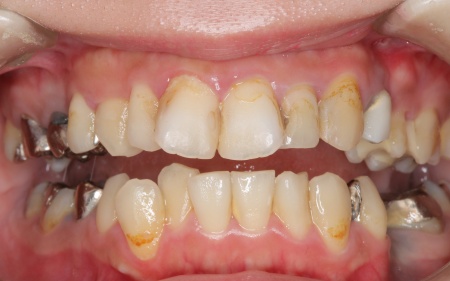

20代女性 ワイヤー矯正で歯並びを整えて虫歯治療やインプラント治療で口腔内全体を改善した症例

診断結果をお伝えしたうえで、以下2つの治療方法を提案しました。 ①歯並びを整えず、必要な部分のみを治療する方法 ②矯正治療で歯並びと噛み合わせの土台を整えたうえで、口腔内全体の治療を行う方法 それぞれのメリット・デメリットをお伝えしたところ、患者様は②の矯正治療を含めた総合的な治療を行う方法を選択されました。 はじめに、歯の表面にブラケットと呼ばれるボタン状の装置を接着し、そこにワイヤーを通して歯を動かすワイヤー矯正を開始しました。治療期間中は定期的に状態を確認し、計画通りに歯が動くよう調整を重ねています。 虫歯が生じている歯に対しては、虫歯部分を丁寧に除去し、歯の形を整えました。その後、被せ物を作製するために型取りを行い、後日完成した被せ物を装着しました。 また、欠損していた左上奥歯1本と左下奥歯1本に対しては、インプラント治療を行います。 すべての治療工程を終えたあと、噛み合わせや見た目、被せ物の使用感に問題がないかなどを確認して、治療を終了しています。 |

治療後